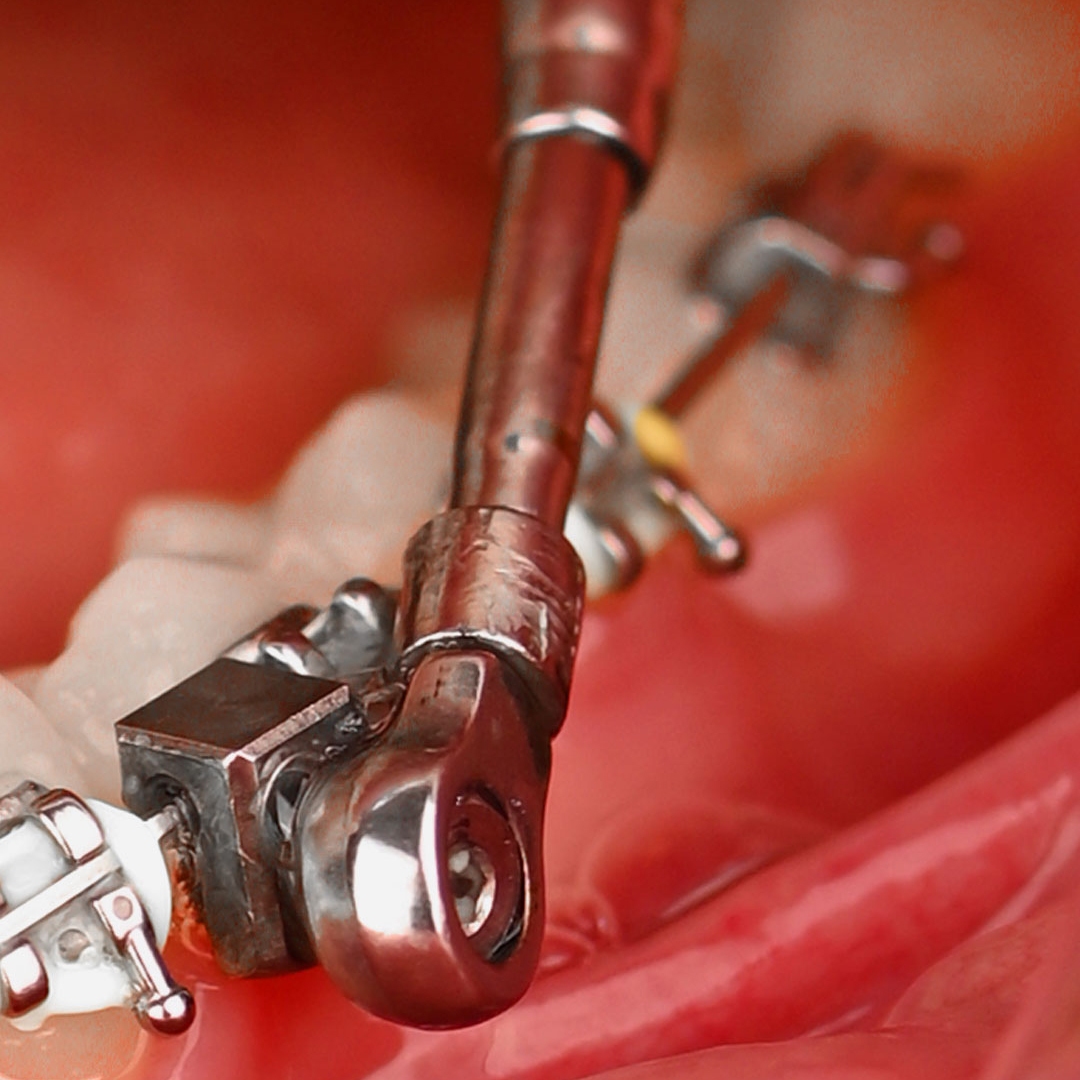

دستگاه ارتودنسی آمریکن ارتودنتیکس PowerScope 2 ( پاور اسکوپ ۲ ) اغلب برای درمان مال اکلوژن های کلاس ۲ استفاده می شود که با اورجت (برآمدگی دندان های جلویی بالا) و اوربایت (همپوشانی عمودی بیش از حد دندان های جلویی بالا و پایین) مشخص می شود. با اعمال نیروی کنترل شده به دندان ها و فک ها، PowerScope 2 می تواند به طور موثری این مشکلات را اصلاح کرده و تراز بایت را بهبود بخشد. این یک دستگاه همه کاره است که هم در کودکان و هم در بیماران بزرگسال قابل استفاده است و آن را به گزینه ای محبوب برای درمان ارتودنسی تبدیل می کند.